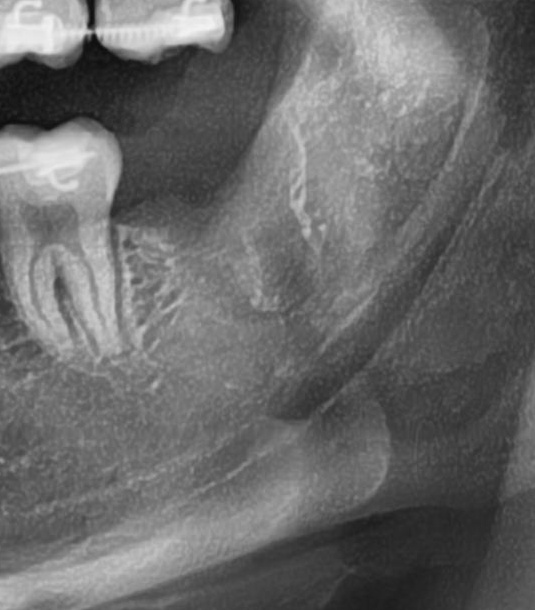

次にパノラマ写真を撮影してみると、左下の親知らずは手前の歯と並んでをまっすぐに生えているのが確認できました。

さらに、下顎の親知らずは下歯槽神経に非常に近いところに生えている場合もあるため、CTで詳しい解析を行います。

親知らずが生えている位置が、神経に近い、あるいは神経に当たっている場合は、大きな病院に紹介する場合もあります。

親知らずの根っこは下歯槽神経から十分に距離があることが分かりました。